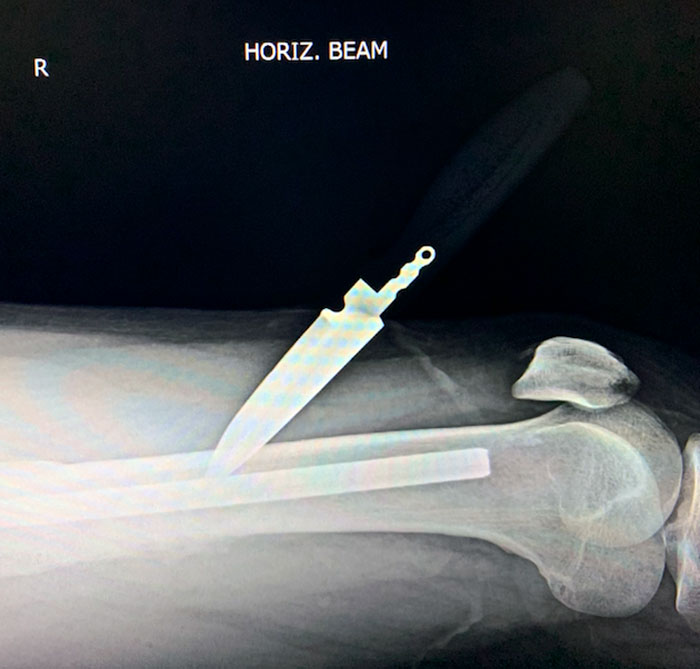

ED Patient From A While Ago Who Stabbed Himself In The Leg - AP Showed The Knife Sitting Around 2 cm Medially To The Femur